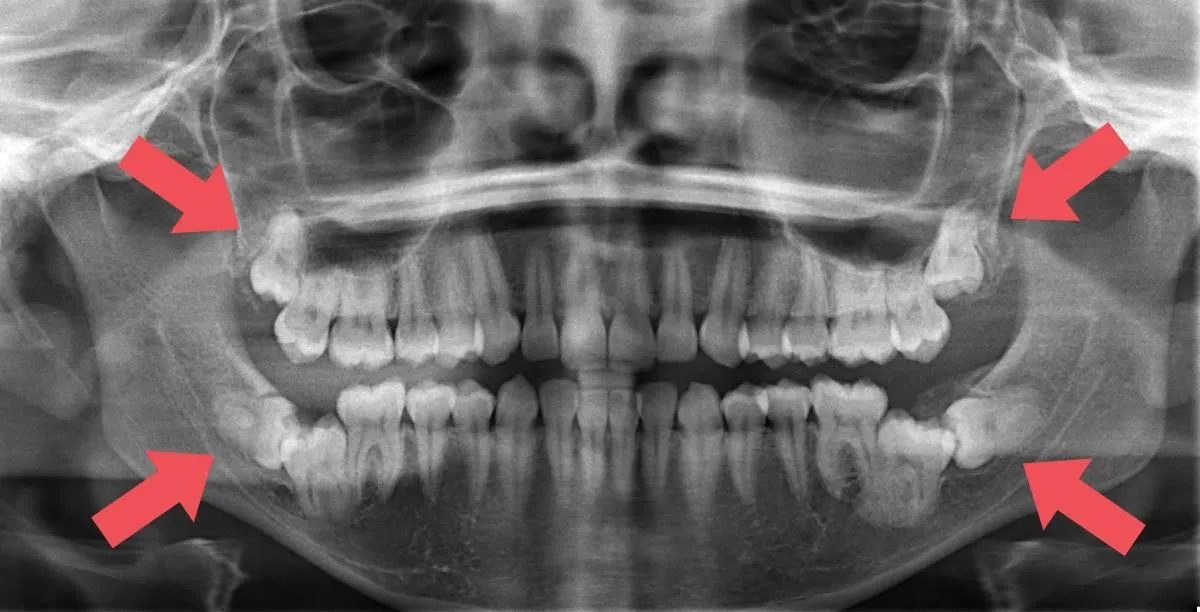

Wisdom teeth typically emerge between ages 17 to 21, which may align with someone considering removable clear aligner treatment. Luckily, painless and asymptomatic wisdom teeth usually won't disrupt clear aligner treatment progress. Your orthodontist can conduct an x-ray examination before fitting your clear aligners to assess any potential issues with wisdom teeth that could affect your treatment. Don't forget to regularly brush your teeth to maintain their health and prevent any unwanted shifts in your teeth.